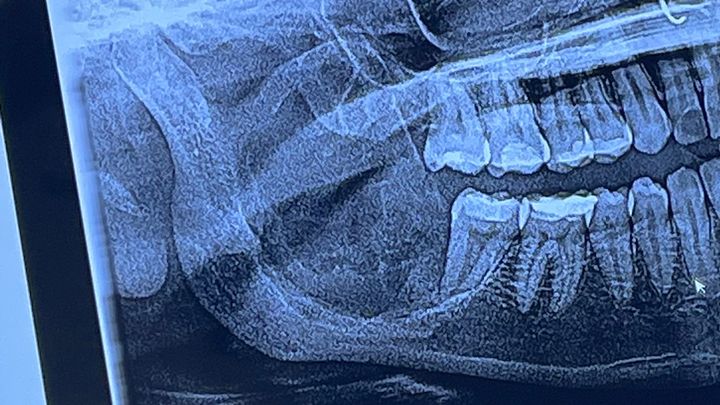

Hi, my name is Janessa, and I’m fundraising for a surgery I need to remove a Ameloblastoma I have in my right jaw. It’s hard for me to afford the surgery. The bone of my jaw on the right side where the tumor is needs to be completely removed and replaced with titanium plates and I also need complete nerve reconstruction. I will lose complete feeling in my bottom lip forever but it’s a sacrifice that has to be made. I need help to be able to afford the surgery. Any donation will be greatly appreciated!